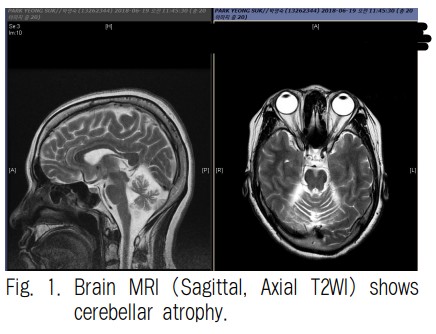

다계통위축(Multiple System Atrophy, MSA)은 뇌와 척수의 여러 신경계가 점차 퇴화하는 진행성 신경퇴행성 질환입니다. 다계통위축은 파킨슨병, 소뇌위축, 자율신경계 이상 등의 증상을 모두 나타낼 수 있습니다. 다계통위축은 전 세계적으로 약 10만 명당 1명으로 알려져 있고, 파킨슨병보다 10분의 1 정도로 드문 질환입니다. 1. 다계통위축 원인 다계통위축의 원인은 아직 밝혀지지 않았지만, 유전적 요인과 환경적 요인이 복합적으로 작용하는 것으로 알려져 있습니다. 1) 유전적 요인 가족력이 있고, 다계통위축과 관련된 유전적 변이가 관련되어 있습니다. 다계통위축 환자의 약 20%에서 알파-synuclein, parkin, leucine-rich repeat kinase 2, ATP13A2 유..